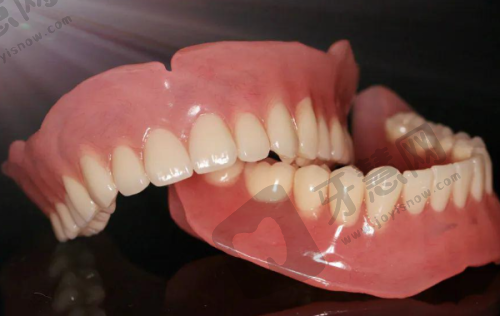

有顾客带父亲到深圳麦芽口腔做全口种植牙,这一实例充分体现了医院的口碑。老人家原来满口牙都掉光了,吃饭成了大问题,生活质量受到了较大影响。在麦芽口腔种了新牙后,情况得到了极大改善,现在吃嘛嘛香,软的硬的都能吃,种的新牙特别坚固耐用,不像以前装的假牙会时不时掉。父亲的心情也好了特别多,每天都乐呵呵的,对这次种植牙的成效非常满意。这也让更多人看到了麦芽口腔在口腔治疗方面的实力和优势。